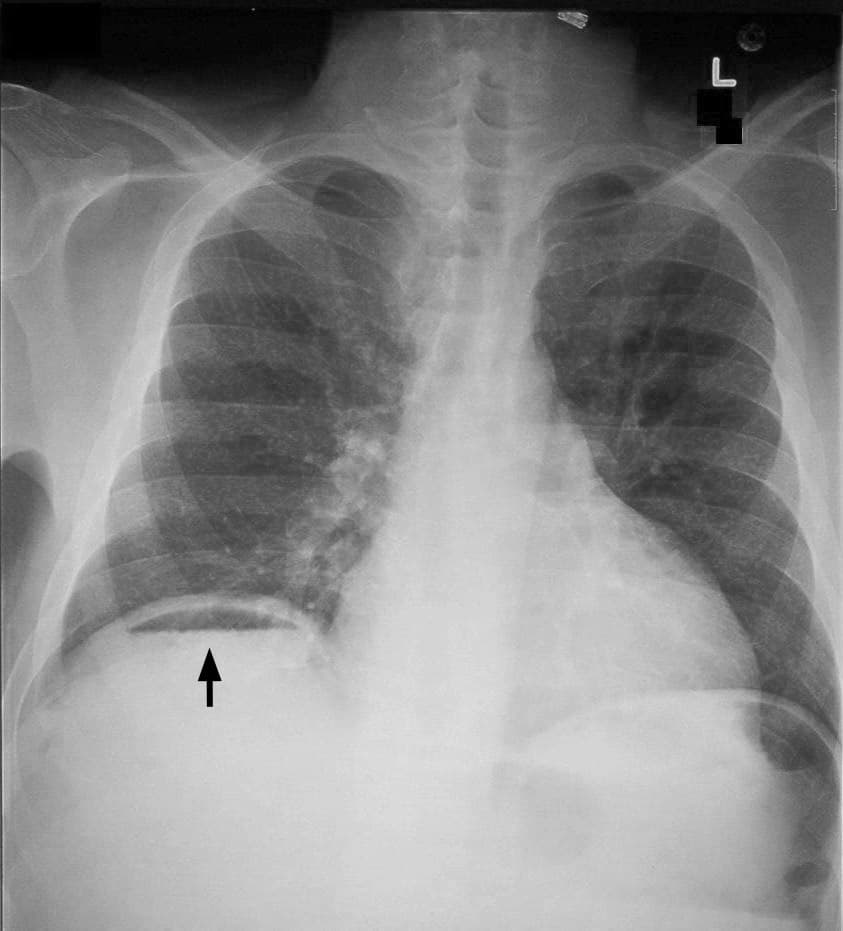

Dans le domaine de la gastro-entérologie, un pneumopéritoine (pneumopéritoine gynécologique, pneumopéritoine pathologique, pneumopéritoine provoqué, pneumopéritonite) correspond à l'entrée d'air ou de gaz dans la cavité de l'abdomen (cavité péritonéale). Cet air provient le plus souvent de la perforation d'un organe digestif creux, tel que l'estomac, l'intestin grêle ou encore le côlon. Il décolle les deux feuillets du péritoine : le feuillet pariétal (qui tapisse la paroi de l'abdomen) ; le feuillet viscéral (qui entoure les viscères abdominaux). Un pneumopéritoine de faible volume est le plus souvent asymptomatique. Il est avant tout suspecté dans un contexte clinique. La radiographie (abdomen sans préparation (ASP) et/ou cliché debout de face, centré sur les coupoles diaphragmatiques) permet généralement de faire le diagnostic, le pneumopéritoine apparaissant comme un croissant radio transparent sous-diaphragmatique, uni ou bilatéral et de taille variable. Cependant, un pneumopéritoine de faible abondance peut facilement passer inaperçu a la radiographie. C'est pourquoi la tomodensitométrie (ou scanner abdominal) est aujourd'hui considérée comme l'examen de référence pour son diagnostic. La tomodensitométrie permet de rendre visible des volumes aussi faibles que d'air ou de gaz. On distingue : le pneumopéritoine pathologique, dont la cause la plus fréquente est la perforation accidentelle ou pathologique d'un viscère abdominal, par exemple à la suite d'un ulcère gastro-duodénal ayant perforé la paroi de l'estomac, ou encore une diverticulite sigmoïdienne perforée. Cependant, toute partie du tube digestif peut également se voir perforée par de nombreuses maladies, dont par exemple une tumeur ou encore un traumatisme abdominal. Le pneumopéritoine rentre alors dans le cadre d'une pneumopéritonite (du grec -itis [-ite], désignant l'inflammation), cas le plus fréquent en pratique médicale. Une perforation de l'appendice provoque toutefois rarement un pneumopéritoine ; le pneumopéritoine provoqué, qui peut être délibérément créé par une équipe chirurgicale en vue d'exécuter une chirurgie laparoscopique.